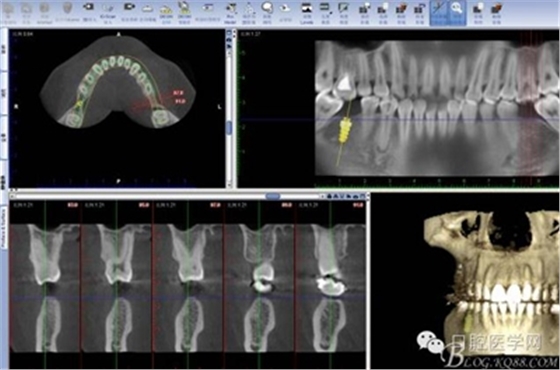

CT

拔除18 28 38 48 后 47 遠中植入支抗釘

因為患者要求半月內(nèi)完成,所以同期植入韓國豋騰4.5*10mm種植體